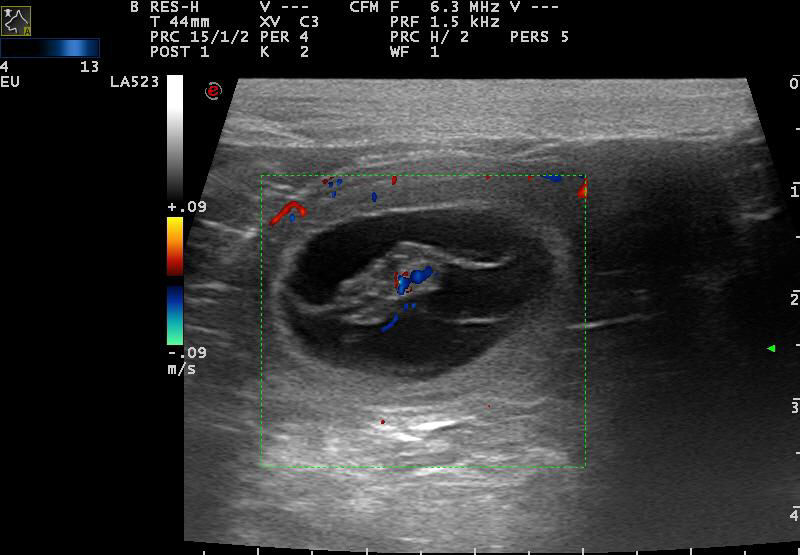

Ultraschall: 26.04.2017: Wow - es hat geklappt! Mejou ist trächtig!